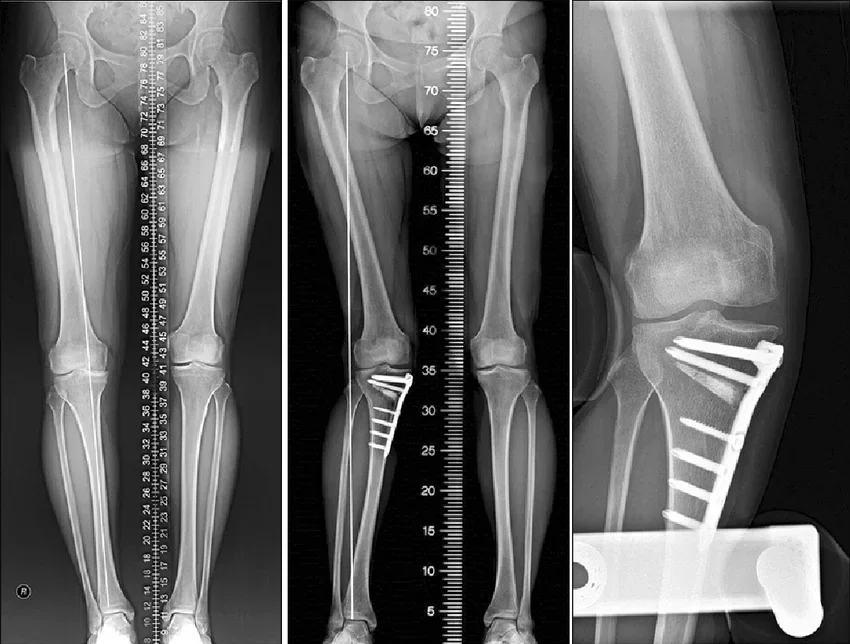

High Tibial Osteotomy (HTO) is a surgical procedure that gently cuts and reshapes the upper part of the tibia to shift weight back to the healthier side of the knee.

How Dr. Siddharth Performs Tibial Osteotomy in Nagpur

Here’s what happens step by step:

- The surgery is done under anaesthesia.

- A small cut is made near the upper tibia (shinbone).

- The bone is carefully opened or closed to correct the angle.

- A small plate and screws hold the bone in the new position.

- The corrected angle allows weight to spread evenly across the joint.

Knee alignment surgery/HTO is a minimally invasive procedure that takes about 1–2 hours. And most patients start walking with support within a few days.

During this time, Dr. Jain’s team supports you with exercise plans, diet guidance, and follow-up X-rays to ensure your knee heals perfectly.

- Use of digital alignment tools and 3D planning for precision